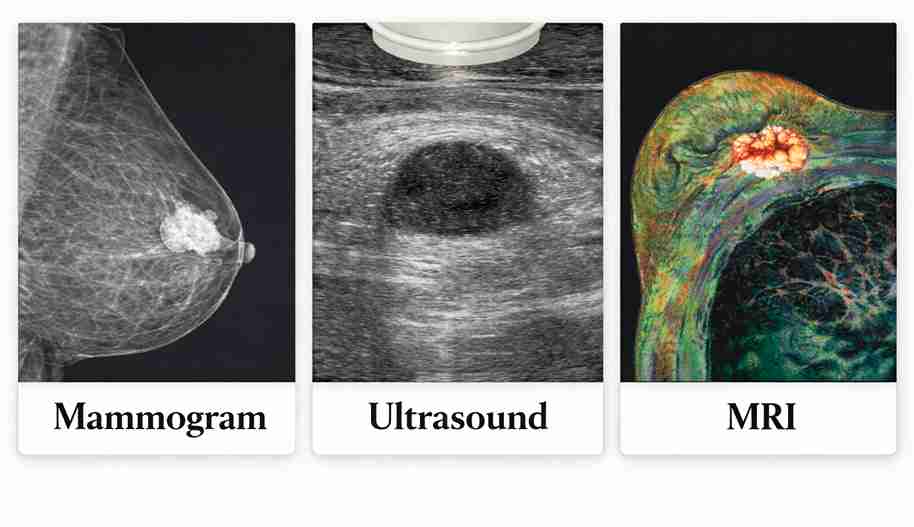

Mammograms are the standard screening tool, ultrasounds assess lumps and dense breast tissue, and MRI is reserved for high-risk or unclear cases, providing detailed imaging when other tests do not give definitive answers.

Breast cancer detection isn’t a one-test game. Mammograms, ultrasounds, and MRIs each serve a specific role based on age, breast density, symptoms, and individual risk. Choosing the right test improves accuracy and reduces unnecessary procedures.

Each test serves a different clinical role. The table below explains the differences between Mammogram, Ultrasound, and MRI:

| Feature | Mammogram | Ultrasound | MRI |

| Best for | Early calcium changes, routine screening | Checking lumps, cyst vs solid | High-risk detail, complex cases |

| Misses | Can be limited in dense breasts | Early calcium changes | Can show false alarms |

| Typical use case | Screening + diagnostic follow-up | Lump evaluation, biopsy guidance | High-risk screening, problem-solving |

| Time | 10 minutes | 15 minutes | 30–40 minutes |

| Comfort | Brief compression | Generally comfortable | Longer, enclosed scan |

| Radiation | Yes, very low dose | No | No |

| Contrast | Not needed | Not needed | Usually required |